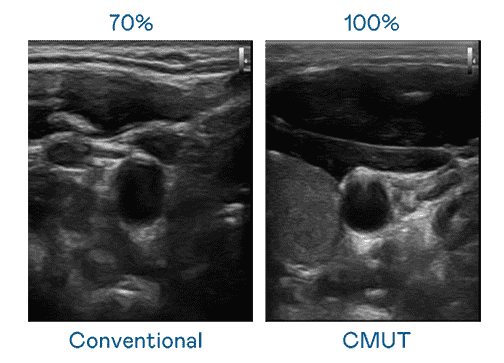

CMUT 技术是一种用电容式微机电元件来产生超音波讯号的技术。。与传统 PZT 压电式技术相比,,CMUT 频宽增加 30%,,,更宽频的超音波讯号让影像解析度大幅提升,,,,是实现高影像品质医疗超音波扫描、、、、促进精准医疗发展的关键技术。。。

大频宽带来超清晰影像

超音波影像的解析度高低,,,,首先取决于探头能发出的讯号频宽。。。。尊龙集团 CMUT 可提供高清晰的超音波讯号,,,提供高频宽、、、、高灵敏度、、、、影像纹理细节更高的超音波影像,,,协助医护人员缩短影像判读时间及利用精准的医疗影像进行诊断。。。。